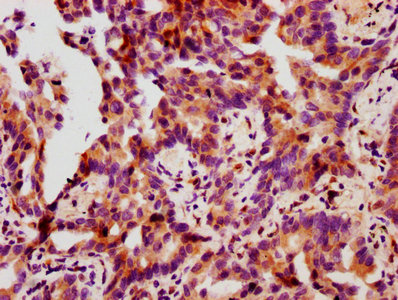

IHC image of CSB-RA010833A78phHU diluted at 1:100 and staining in paraffin-embedded human lung cancer performed on a Leica BondTM system. After dewaxing and hydration, antigen retrieval was mediated by high pressure in a citrate buffer (pH 6.0). Section was blocked with 10% normal goat serum 30min at RT. Then primary antibody (1% BSA) was incubated at 4℃ overnight. The primary is detected by a biotinylated secondary antibody and visualized using an HRP conjugated SP system.